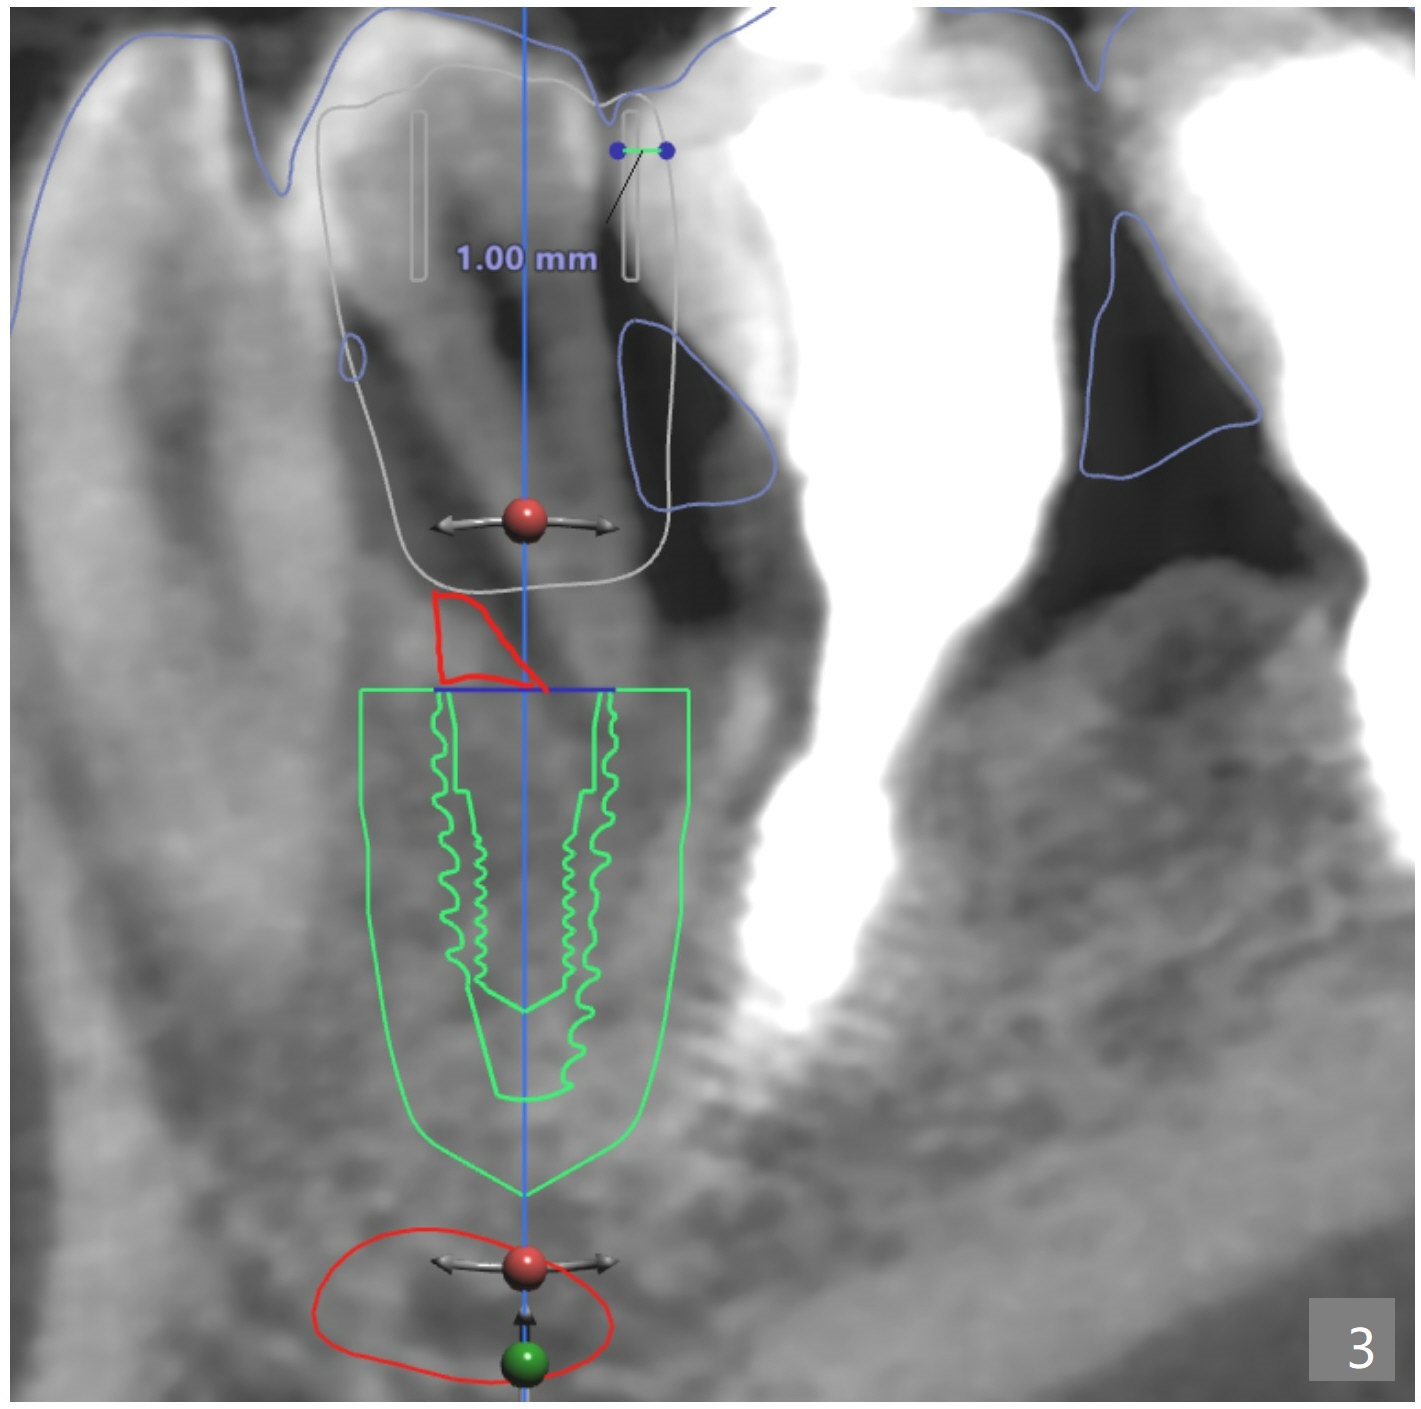

A: I see. I reviewed the case again and is it okay if I put another screenshot for you to show you how much to trim (same as the planning software, Fig.1).

And the reason of implant deviation towards distal is not because of we planned to adjust the mesial contact of #20. Adjusting the contact is only for guide insertion. Due to insufficient space for narrow metal sleeve, adjusting the mesial contact of #20 was suggested. When you look at the inner part of the surgical guide, those inner parts of interproximal are holding the guide steady during the osteotomy (Fig.2). Again, adjusting the contact does not mean that the whole guide will be shifted to that side, but only for the path of insertion.

I am guessing the reason of the deviation would be the slanted surface of the bone. And when you see the red marked site (Fig.3), that shows white color (which also means dense bone). If there was more space, we could've used a regular metal sleeve and plan for a bone trimmer prior to the initial drilling, but this case, we couldn't do that. Narrow metal sleeve was used with 12mm of max offset. So, in this kind of case, I am sorry to tell you but we might have to manually remove the excessive bone to flatten the bone surface for osteotomy before implant placement when the regular bone trimmer can not be used.